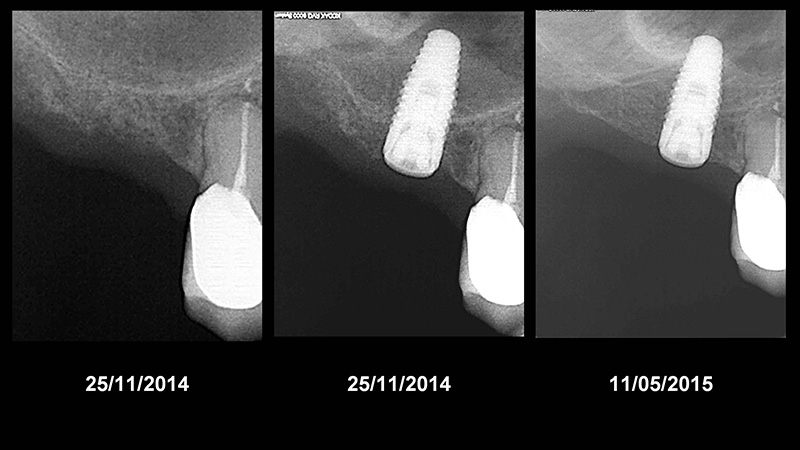

Évolution radiologique d’un environnement osseux péri-implantaire après un protocole d’extraction puis implantation.

Évolution radiologique d’un environnement osseux péri-implantaire après un protocole d’extraction, puis implantation/comblement sinusien. Notez le gain osseux après seulement 6 mois.

Le même cas 3 ans après, avec couronne mise en place.